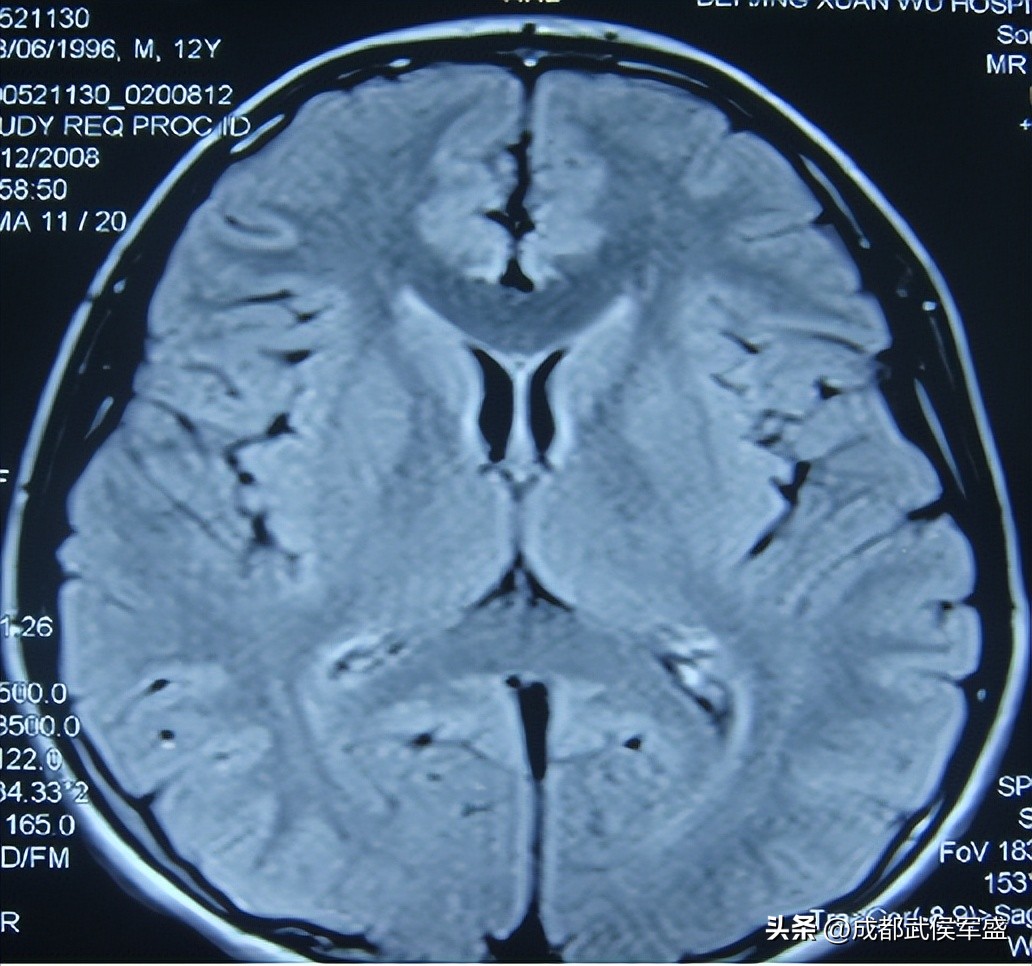

但是是否可以进行手术是需要专家进行评估的,因为癫痫手术需要切除致痫灶,所以必须先判断患者脑内的致痫灶是否单一、致痫灶所在位置是否在重要功能区,如果致痫灶过于分散或致痫灶在重要功能区,那么是不建议进行手术的。还需要知道的是,手术是会造成创伤的,所以术后会有引发外伤性癫痫的可能。